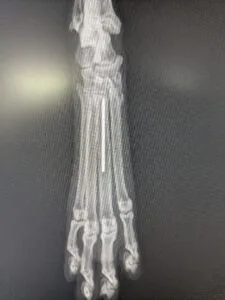

犬の中手骨・中足骨骨折について|症例をもとに治療法と注意点を解説中手骨/中足骨骨折

骨折しやすい手の甲・足の甲部分である中手骨・中足骨に起こる骨折。今回はその分類「中手骨/中足骨骨折」の症例をもとに、治療の流れと術後のケアをわかりやすく解説します。